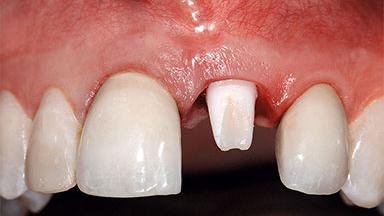

A healthy 37-year-old female patient was referred for a consultation on the replacement of missing tooth 21 with an implant-supported restoration. She stated that several years previously the tooth had been traumatically avulsed following a motor vehicle accident. The tooth was replaced with a three-unit fixed partial denture (FPD) immediately afterwards. Over time, she became disillusioned with the FPD and looked for a different option, including orthodontic therapy. She presented still in her orthodontic appliances, with the pontic sectioned free from the FPD but attached to the archwire. Her orthodontist felt that orthodontic treatment had been successfully completed, but nevertheless referred her before removing the appliances in case adjustments were necessary.

Type of Implants Two-Piece

Abutment Type CAD/CAM